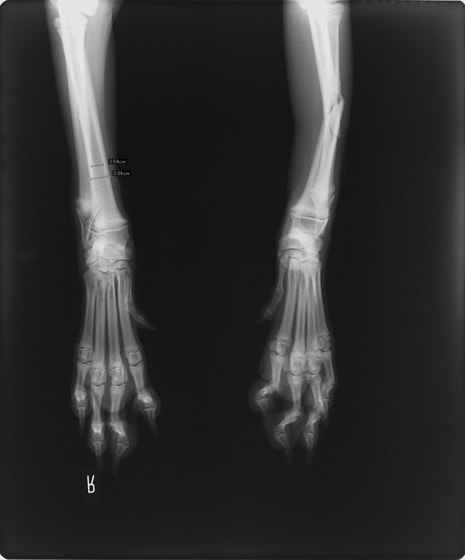

トイプードル 右遠位橈尺骨短斜骨折のALPSによる内固定